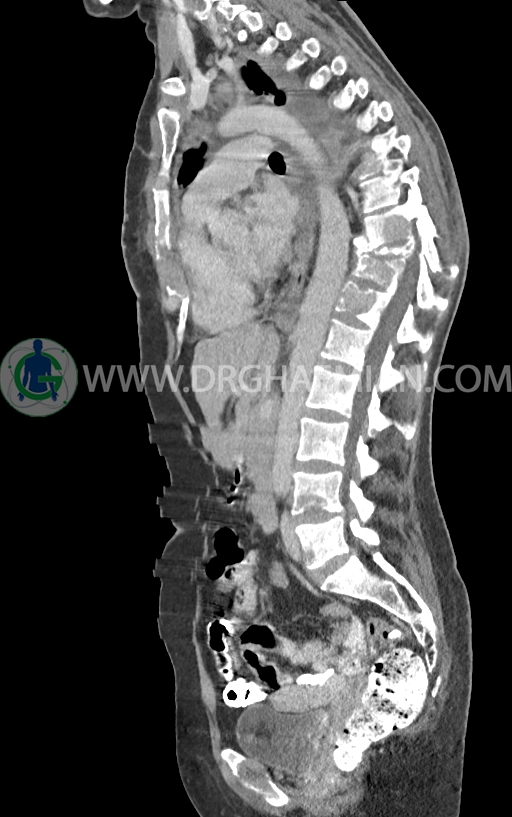

در سی تی اسکن اسپیرال ریه و مدیاستن -شکم و لگن با کنتراست خوراکی و وریدی (مولتی دیدکتور 16 با مقاطع ظریف و بازسازی های ساژیتال و کرونال) :

–ضایعات استخوانی لیتیک فراوان منتشر در تمامی طول ستون مهره و لگن رویت شدند که مطرح کننده متاستاز استخوانی می باشند.

–شکستگی پاتولوژیک در مهره های T6 , T10 , T11

–کیفوز موضعی در Level T10 , T11 در ستون مهره

–رتروپالشن شکستگی مهره T10 همراه با ایجاد تنگی کانال نخاعی

ضایعه ای در مثانه، رحم، تخمدانها و آدنکس ها مشهود نیست.

ضایعه ای در کبد، کیسه صفرا، مجاری صفراوی، طحال، کلیه ها، پانکراس و آدرنالها مشهود نیست.

کلیه ها کنتراست را ترشح کرده اند و نمای سیستم پیلوکالیسیل و حالب دو طرف نرمال است .

مایع آزاد در حفره شکم و لگن رویت نمی شود.